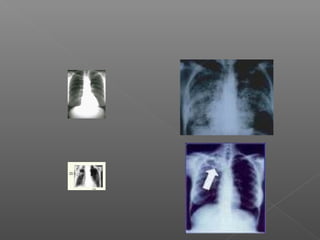

 La inflamación parenquimatosa inicial no suele ser visible en

Rx de Tórax. Se observa un infiltrado localizado inespecífico

antes del desarrollo de hipersensibilidad Tisular.

los bacilos en la Rx de Tórax se observa un

-Patrón Miliar con pequeños nódulos

distribuidos uniformemente.

 La radiografia:

Suelen mostrar infiltrados extensos o

cavidades de paredes gruesas en los

lobulos superiores.